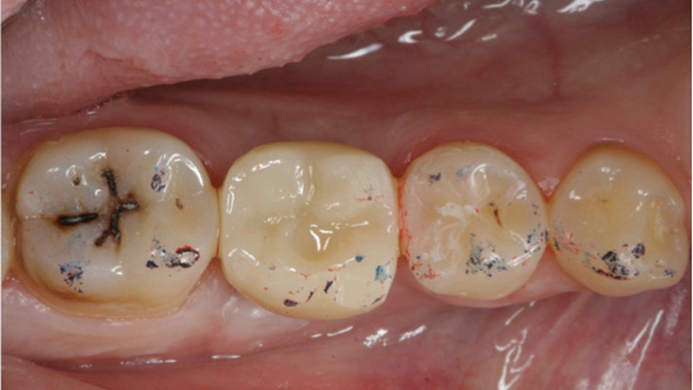

Clinical case: Delayed implant placement: sinus floor elevation by means of lateral

approach & implant placement with GBR

- Courtesy of Dr. Irfan Abas, Netherlands -